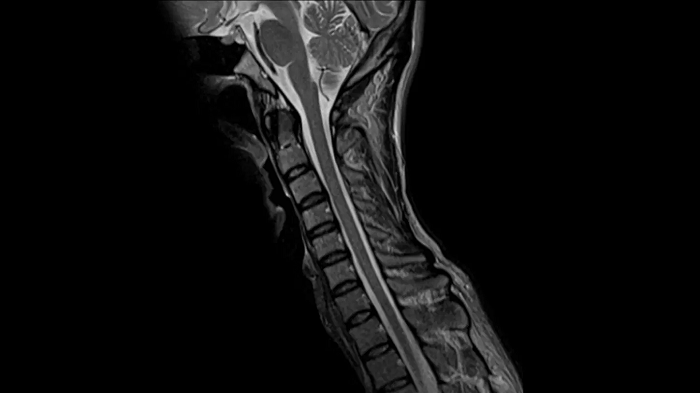

Spine

T2 TSE

Exceptional C-Spine images with T2 TSE with the use of the Head/Neck coil.

Deep Resolve Gain & Sharp

0.5 x 0.5 x 3.0 mm2

TA 3:28 minutes

MAC-ID: 7aaaa0164. Image Credit: Siemens Healthineers